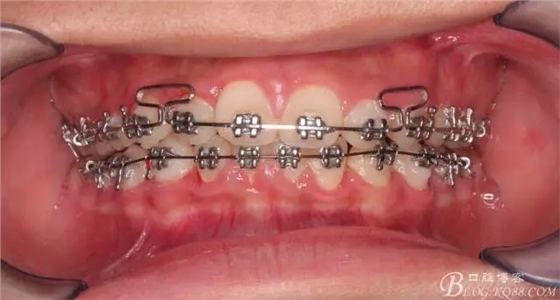

一晃快兩年了,我覺得關節(jié)重建及咬合穩(wěn)定,再加上患者的急迫愿望,我們拆除了矯正器。

尖牙關系中性,磨牙關系中性,咬合鎖結良好!